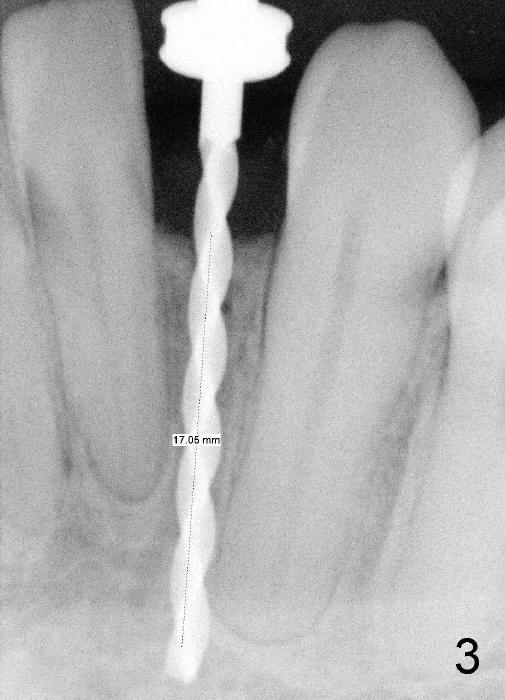

Informed consent is obtained with emphasis of potential damage to the neighboring roots. Two PAs have to be taken with the first pilot drill (1.5 mm) in place for determination of initial trajectory (Fig.2,3). Osteotomy is enlarged coronally with 2 mm pilot drill. Finally a 3x17 mm one piece implant is placed with primary stability, determined tactilely (Fig.4). Immediate provisional is fabricated. To avoid micromovement, the immediate provisional (Fig.5 P) is bonded to the neighboring teeth with composite (*); it is further fixed in place with a lingual retainer (Fig.6 arrowhead).